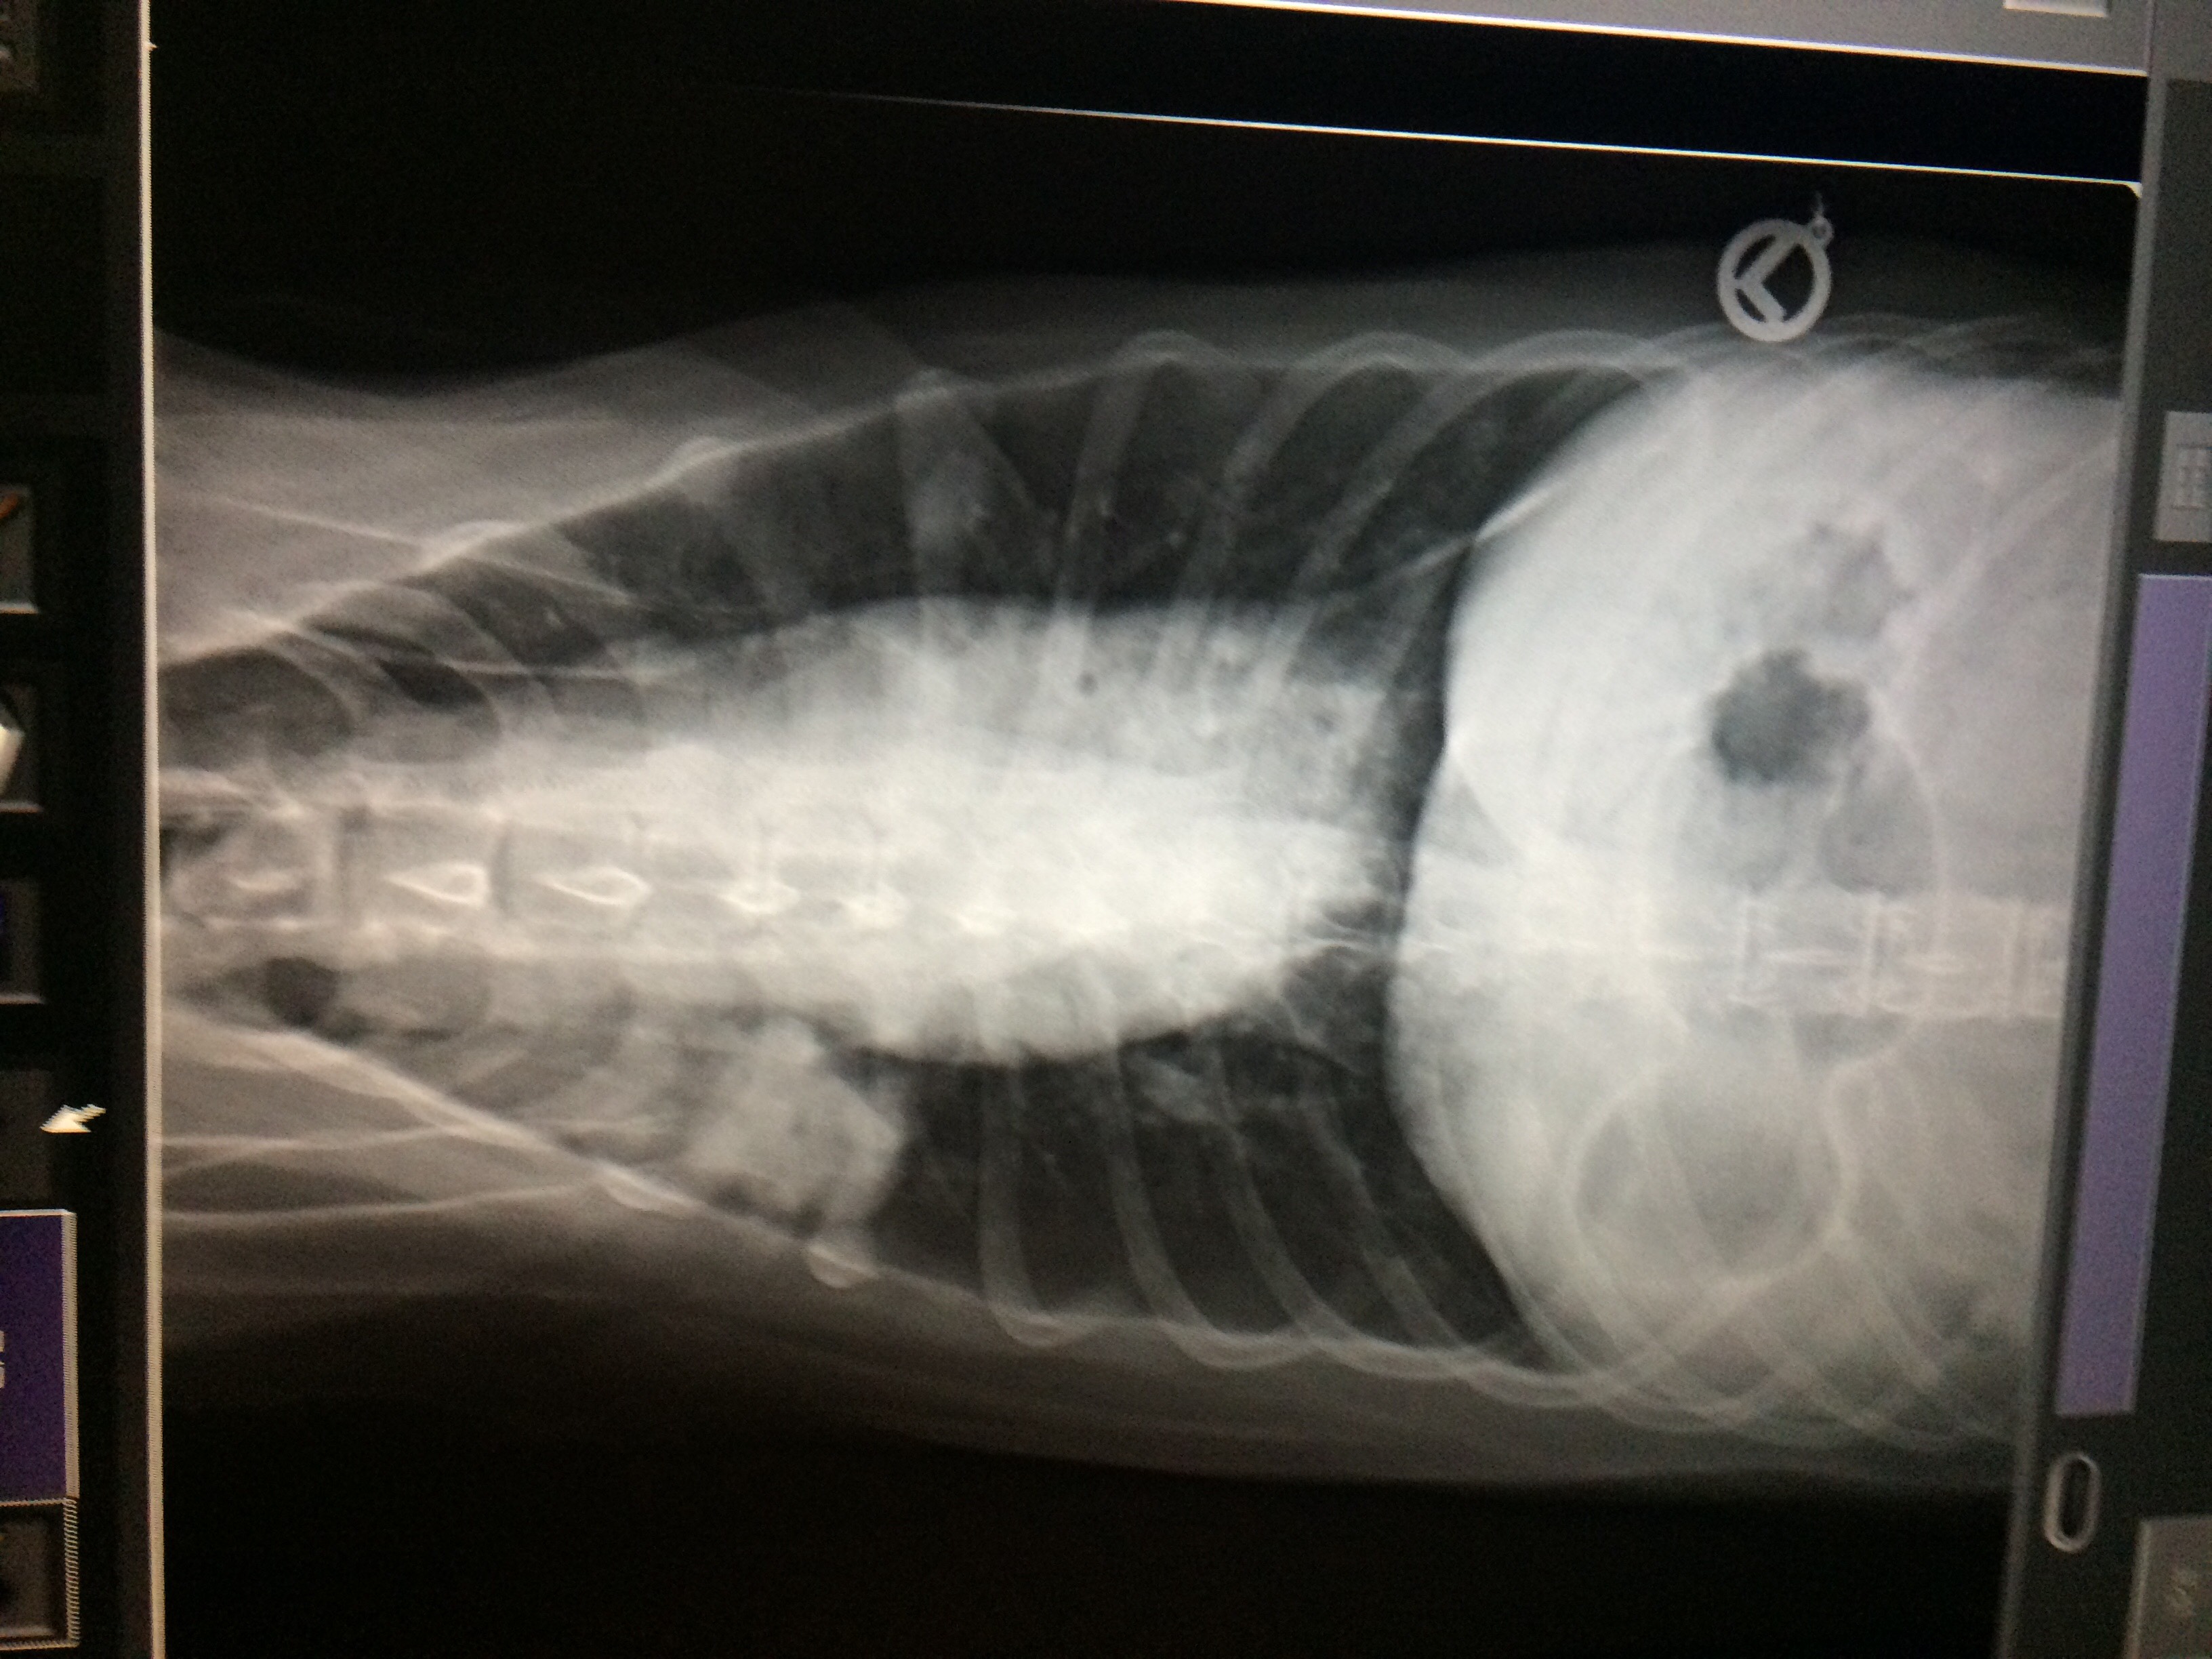

Ihr zwischenwirt ist die schnecke. Bei der lungenzeichnung, die sie sehen, handelt es sich um eine alveoläre lungenzeichnung. Hjertelungeorm hjertelungeorm er meget almindelige i danmark og især i københavnsområdet. Weltweit > 700.000 neue fälle / jahr 1 todesfall/min bedingt durch 1 lungentumor hund und katze selten inzidenz hund: Wenn der lungentumor ihres hundes metastasiert ist, ist es für ihren hund fast unmöglich, ohne krebs zu kommen, da der krebs bereits in den gesamten körper des tieres eingedrungen ist. Der lungenwurm des hundes ist ein parasit der lunge, der atemwege und darüber hinaus auch der blutgefäße.

Bei der lungenzeichnung, die sie sehen, handelt es sich um eine alveoläre lungenzeichnung. Lungenwürmer bei hunden sind parasiten, die in bestimmten entwicklungsphasen die lunge, atemwege oder auch blutgefäße des hundes besiedeln. Einer masse in der milz an einem.

Anders als bei den übrigen lungenzeichnungen weist die alveoläre lungenzeichnung ein. Home » lungenentzündung beim hund: Onkologie auf den punkt gebracht:

Radiographic characterization of primary lung tumors in 74 dogs. Bei der lungenzeichnung, die sie sehen, handelt es sich um eine alveoläre lungenzeichnung. Primäre tumoren der lunge bei hunden.

[ad_1] lungenkrebs bei hunden kann primär sein, d. Nicht immer steckt hinter einem milztumor jedoch ein hämangiosarkom! Bei der lungenzeichnung, die sie sehen, handelt es sich um eine alveoläre lungenzeichnung.